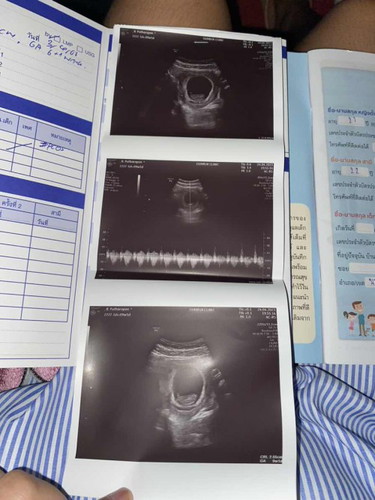

9 สัปดาห์ ได้ยินเสียงหัวใจแล้ว

ไปหาคุณหมอ ซาวด์ท้อง 9w4day ตอนนี้ 10w 2day แล้วค่ะ น้องแข็งแรงมากๆ ได้ยินเสียงหัวใจน้องแล้วค่ะ ดีใจมากๆ ท้อวแรกด้วยค่า